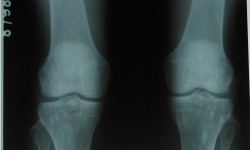

Osteo poikilosis with Osteopathia striata (Overlapping syndromes)

By Admin | September 30, 2013 - 7:23 am | Musculoskeletal, Skeletal Dysplasias

Both knee-A P View